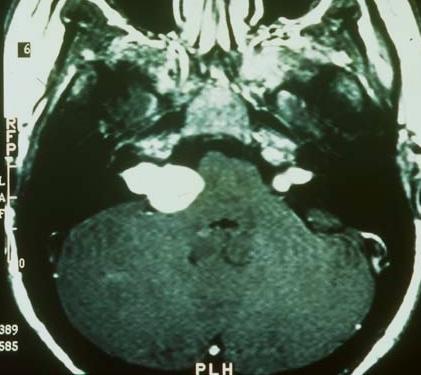

2. What does the MRI scan below show?

Figure 1